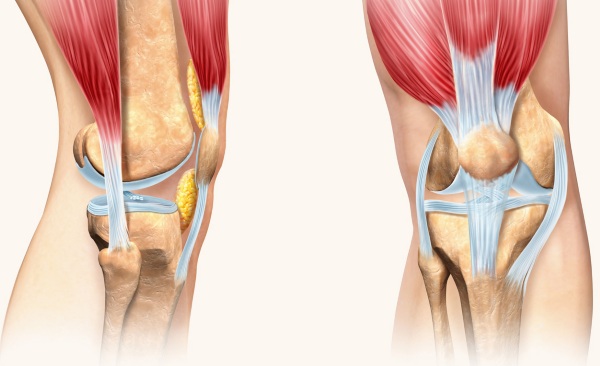

По форме сочленение относится к мыщелковым. В его формировании участвуют 3 костные структуры, поэтому сустав называют сложным. В коленном суставе сочленяются мыщелки бедра, суставная поверхность большеберцовой кости и надколенник. Малоберцовая кость в состав колена не входит.

Сочленяющиеся поверхности неидентичны по площади и форме. Чтобы этого достичь, в составе колена имеются хрящевые мениски. Кроме того, фиксируется сустав многочисленными связками.

Выделяют внесуставные и внутрисуставные связки. К первой группе относят коллатеральные большеберцовую и малоберцовую, поддерживающие связки надколенника, косую и дугообразную.

Связки коленного сустава (анатомия околосуставных структур более разнообразна) внутри сустава менее разнообразные. Внутрисуставной аппарат представлен 2 важными крестообразными связками: передней и задней. Эти структуры участвуют в биомеханике сустава при его активных движениях.

Речь идет об образованиях из грубой волокнистой ткани. По форме они напоминают серп или полумесяц. В полости коленного сустава 2 мениска: латеральный и медикальный. Они обеспечивают достижение высокой конгруэнтности сустава.

Описываемые хрящевые образования имеют тело и 2 рога: передний и задний. Если посмотреть на них сверху, то латеральный мениск напоминает букву “О”, в то время как медиальный напоминает “С”. Соединены между собой эти структуры посредством поперечной связки колена.